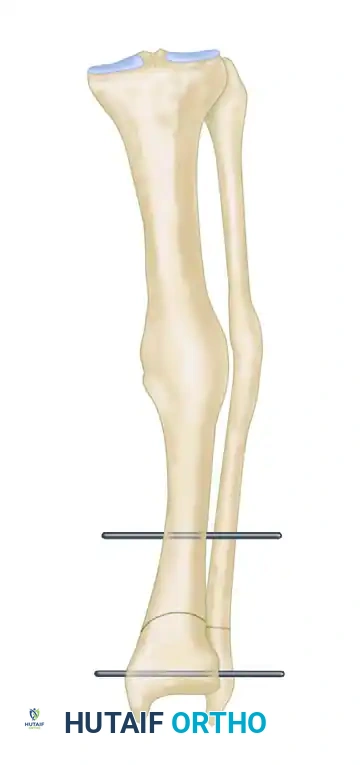

- Osteoclasis and Correction: With a broad osteotome, complete the tibial osteotomy through the posterior cortex. Correct the varus or valgus deformity by manipulating the distal fragment until the two threaded pins are perfectly parallel to one another.

FIGURE 58-11B: Osteotomy is completed, and pins are brought parallel to correct the varus or valgus deformity.